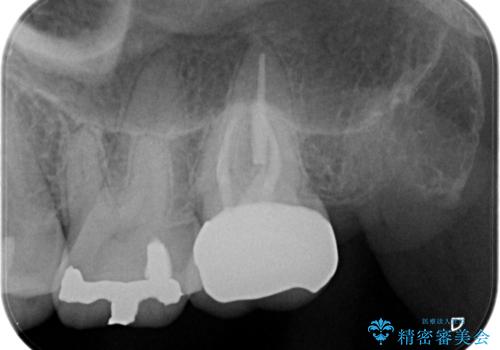

【精密根管治療】奥歯がズキズキ痛い。

- 奥歯がズキズキ痛いことを主訴に来院されました。

治療にて歯髄は保存できないと判断したため、根管治療を行いセラミッククラウンにて修復しております。

自発痛の既往がある場合は、抜髄の適応となることが多いです。